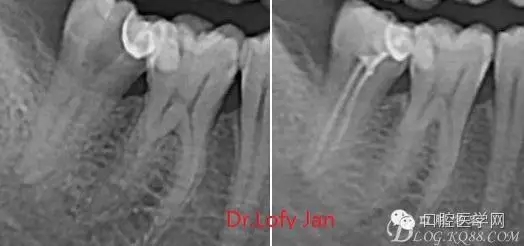

①有助于發(fā)現(xiàn)牙體和根尖周組織的異常改變,如牙折、牙內(nèi)吸收、髓腔鈣化及根尖囊腫;

②有助于確定牙根和根管的數(shù)目、位置、形態(tài)、方向和彎曲情況;

③有助于了解以前曾作過的治療情況,為再治療提供依據(jù);

④在操作前估計根管的工作長度;

⑤評價根管充填的質(zhì)量以及療效。

病例分析:曲面斷層片在x線輔助診斷與檢查中目前大多數(shù)文獻(xiàn)和著作都建議只能作為初診拍片檢查手段,不能作為終末疾病的確診與手術(shù)療效的評價指標(biāo),臨床大部分中小型門診都因為設(shè)備不齊全導(dǎo)致信息偏差很大。